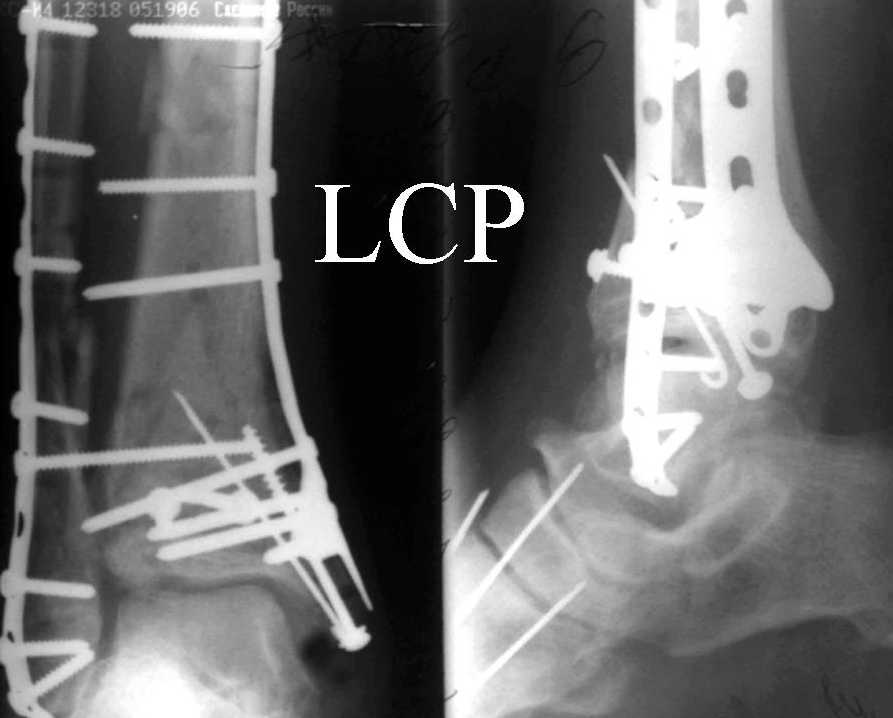

Дрягин В. 03 Январь 2007, 19:11

Посмотрим вроде прошло если понравится напишите расскажу как это сделать.По принципам АО кстати при поступлении сначала восстанавливают длину малоберцовой кости фиксируют пластиной 1/3 трубки потом накладывают аппарат наружной фиксации и через 7-10 дней открыто восстанавливают большеберцовую кость.С уважением Дрягин

На рентгенограммах типичный перелом пилона по типу С-3. есть опыт до 100 открытых опреаций у нас в клинике. 20 примерно в год. Принцип один -все внутрисуставные переломы нуждаются в открытой репозиции и внутренней стабильной фиксации. При поступлении КТ не надо, так как получается только нагромождение костей. Истинной картины нет. Главное восстановить длину малоберцовой кости - это ключ к успеху. При поступлении меньше всего надо думать о сосудистых расстройствах, т.к. сама операция и репозиция даже сначала частичная даёт улучшение сосудитых нарушений. Причём очень быстро. Операция в 2этапа. При поступлении доступ позади наружной лодыжки, причём обязательно. После этого репозиция малоберцовой кости и фиксация пластиной 1/3 трубки под винт 3,5. Дренаж и любой аппарат наружной фиксации. Затем после спадения отёка на 5-7-10 день аппрат снимается и дугообразный разрез спереди от медиальной лодыжки 10-12 см. Главной чтобы расстояние между 1 и вторым разрезом было не меньше 7-8 см. Тогда не будет некрозов лоскутов. Таранная кость используется как матрица на неё укладываются отломки и фиксируются пицами. Ренг-контроль. Отломки лежат все отдельно, но ничего не высыпется. При переломах С-3 всегда нужна костная пластика (из крыла). Фиксация пластиной лист клевера простой или LCP. Гипс не нужен. Дренаж до 48 часов. Операция длится 3-4 часа обязательно без жгута. Посылаю примерно такой же случай.